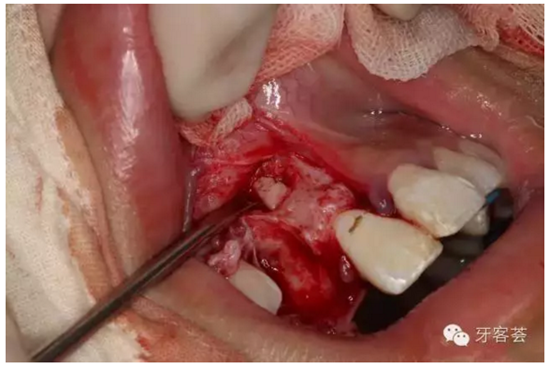

圖14:超聲骨刀去骨約5mm范圍,暴露折斷的根尖1/3.

圖15:微創(chuàng)牙挺取出根尖1/3斷根。

圖16:超聲骨刀清理骨腔周圍組織